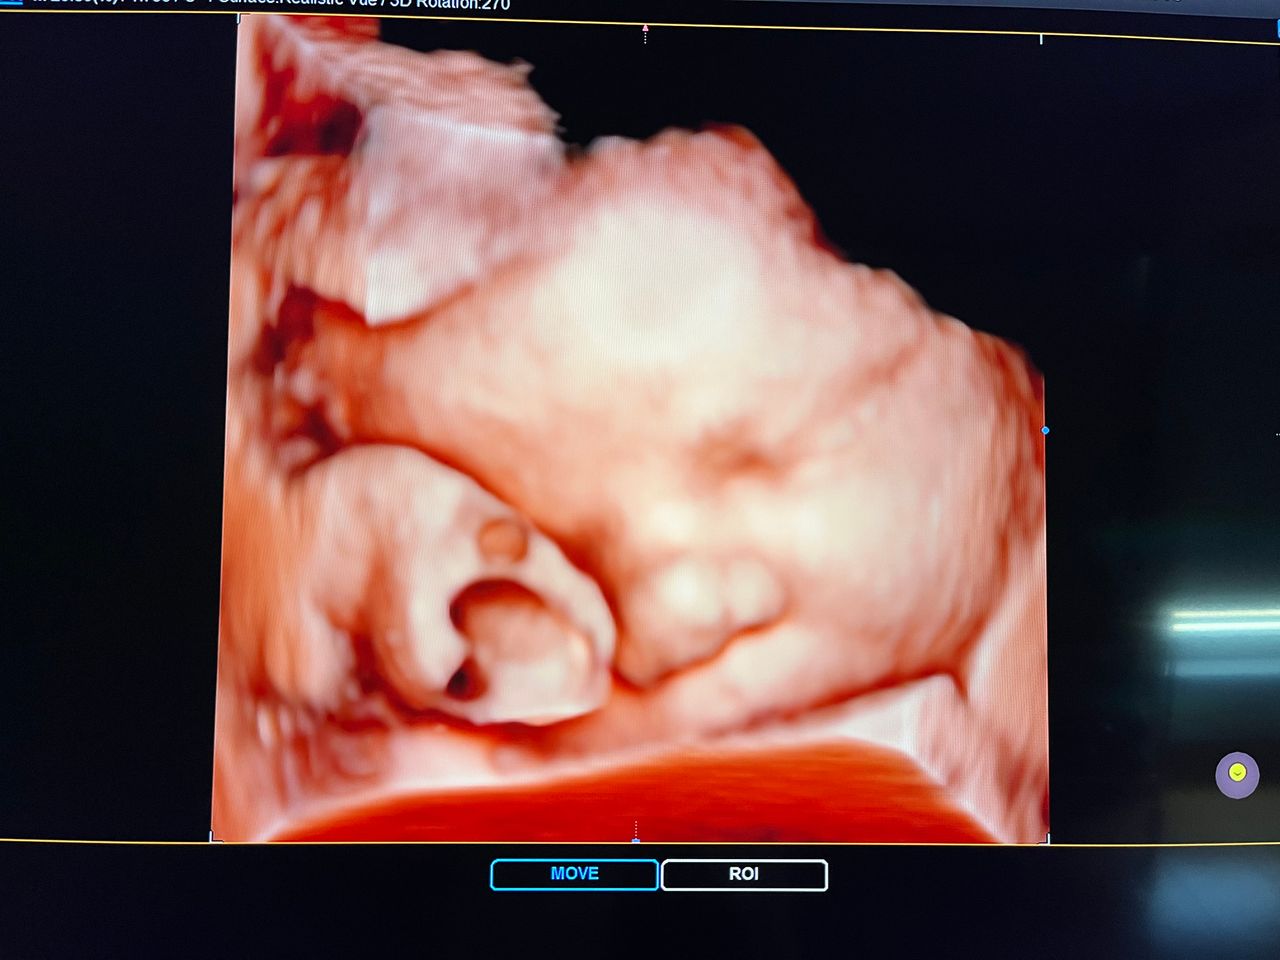

Attualmente lavoro come Dirigente medico nella SC di Ostetricia e Ginecologia dell'Ospedale Michele e Pietro Ferrero di Verduno, mi occupo prevalentemente di screening prenatale, ecografia ostetrica del I trimestre( misurazione translucenza nucale,NT), ecografia morfologica del II trimestre, ambulatorio pregresso taglio cesareo, ecografia ostetrica 3D. Seguo le gravidanze fisiologiche e quelle ad alto rischio , presto servizio in sala parto. Eseguo visite ginecologiche di I-II livello in regime ambulatoriale, counseling contraccettivo ed eventuale prescrizione pillola, inserimento spirale (IUD), dispositivo sottocutaneo (Nexplanon).

Foto e video